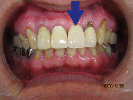

歯がこのままではダメだと思い、一念発起された50代女性の方です。

もちろん治療期間が長期にかかることも、治療費が高額になることも、外科的な手術が何度か必要であることなど、

インプラント治療と咬み合わせ治療のほぼ全てを大名歯科ホームページで予め知っていただいた上で決心され来院されたそうです。

インプラント治療は顎骨が乏しかったため、増骨手術も併用しなければならない難症例でした。

治療期間中は残存歯数が少ない上に、丈夫でないため生活に不自由な点がでました。

さらに咬み合わせが安定しにくい症例のため、プラスチック仮歯がよく壊れたり、外れたりして、修理に来院していただくなど大変な苦労とご迷惑をおかけしました。

審美性(見た目)は十分回復できたと思っており、患者さんも大変満足されています。

食事は当然のことかもしれませんが、よく咬めるようになったそうです。

咬み合わせ治療は非常に難しいため、これで十分かどうか分かりませんが現在もこのまま定期的なメインテナンス中です。